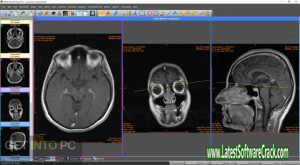

DICOM Viewer Pro is a professional DICOM image viewing software, equipped with many features that can help you analyze and manipulate DICOM images. The software supports a wide range of DICOM files, including raw images, JPEG files, and compressed DICOM files. With DICOM Viewer Pro, you can open and view multiple DICOM files simultaneously, compare two DICOM images side-by-side, make measurements and annotations on DICOM images, print DICOM images, and more.

Sante DICOM Viewer Pro is a professional DICOM image viewing software, w hich offers advanced features and options for both medical professionals and general users alike. With this program you can open and view DICOM files, as well as various other types of image files, including JPEG, PNG, TIFF, and more. The software also provides tools for measuring and annotating images, making it an ideal tool for both diagnostics and research purposes.

Sante DICOM Viewer Pro is a professional DICOM image viewer, anonymizer, converter, and editor. The program offers a great number of features that allow users to view, edit, and analyze DICOM images. The program is able to read and display all common DICOM formats, including JPEG, TIFF, PNG, BMP, GIF, and AVI. In addition, the program supports all popular PACS servers and can be used as a standalone DICOM viewer.

Sante DICOM Viewer Pro 12.1.5 is a professional and powerful software for viewing medical images and video files. This program provides users with the ability to view 2D, 3D, and 4D images. In addition, this software supports all modalities such as CT, MRI, X-Ray, PET, and more. The Sante DICOM Viewer Pro 12.1.5 also provides users with a wide range of measurement tools, which can be used to accurately measure various areas in an image.

Sante DICOM Viewer Pro is a professional DICOM image viewer, editor, converter, and manager with an advanced medical image processing engine. The software offers a unique combination of features to view, edit, annotate, measure, print, and export images in an easy-to-use interface. It supports all major DICOM formats and works with all common modalities such as X-Ray, CT, MR, USG, and more.

Sante DICOM Viewer Pro is a professional DICOM image viewer, anonymizer, converter, editor, and exporter that comes with an intuitive user interface and support for all the common editing tools. With Sante DICOM Viewer Pro you can open single images or sets of images stored in DICOM format. The program also lets you export your images to JPEG, TIFF, PNG, PDF, or DICOM format.

With Sante DICOM Viewer Pro, you can make the most of your medical images in no time. The software provides a user-friendly interface and loads images quickly for easy viewing. You can also use it to annotate, measure, and markup your images for better clarity. Plus, with its advanced tools, you can enhance image quality, adjust colors, and more. And if you need to share your images with colleagues or patients, Sante DICOM Viewer Pro lets you export them in various formats, including JPEG and PDF.